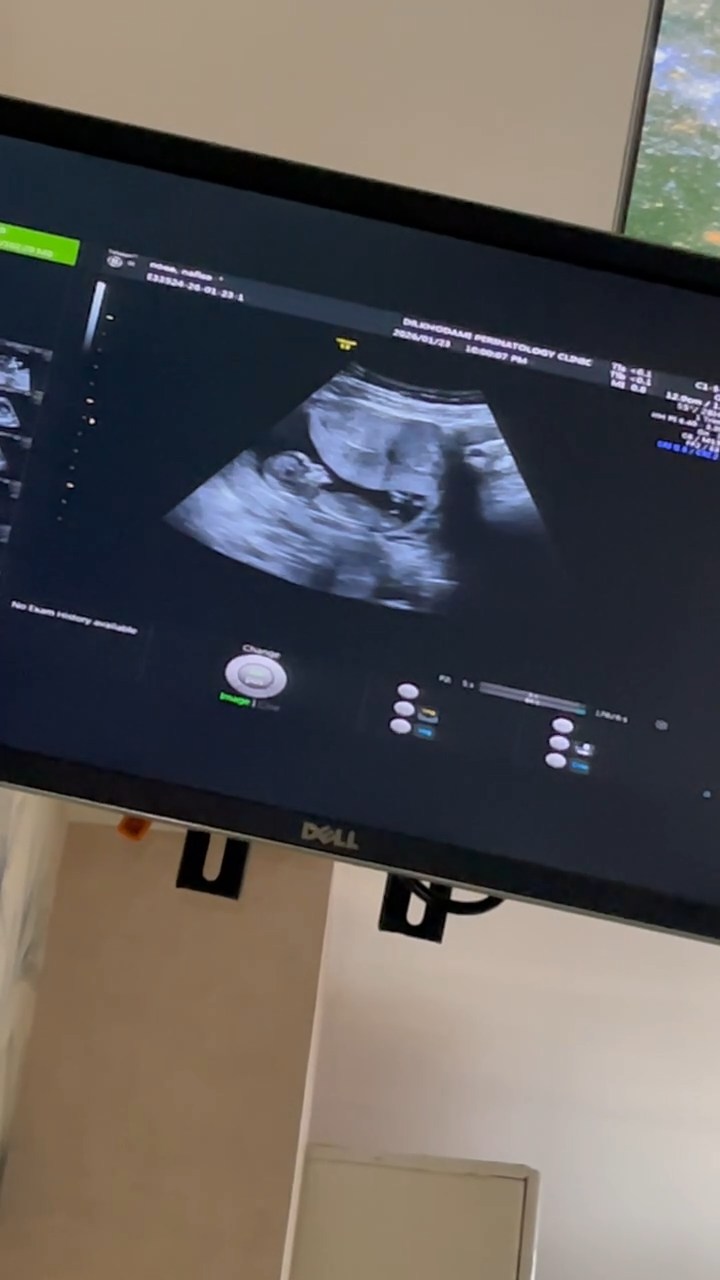

minmax27 مدیر استارتر عضویت: 1404/10/26 تعداد پست: 14 عنوان جنسیت بچه 40 بازدید | 14 پست این عکس از سونوی nt گرفتمراجع به جنسیت هیچی نگفت دکتر امروز | 16:17 0 نفر لایک کرده اند ... گزارش تاپیک نامناسب

minmax27 مدیر استارتر عضویت: 1404/10/26 تعداد پست: 14 عکس از برگ سونوگرافیت بده چند هفته انتی دادی ۱۲ هفته و دو روز

minmax27 مدیر استارتر عضویت: 1404/10/26 تعداد پست: 14 من متوجه نشدمچند هفته رفتی؟ ۱۲ هفته و دو رپز بودم

minmax27 مدیر استارتر عضویت: 1404/10/26 تعداد پست: 14 فک میکنم پسره حتی احتمال هم نداد بهت؟ ازش پرسیدمگفت نه مشخص نیستحتی دکتر خودم هم نشون دادم اونم گفت چیزی درمورد جنسیت بهت نگفت؟گفتم نهدکتر خودمم چیزی نگفت